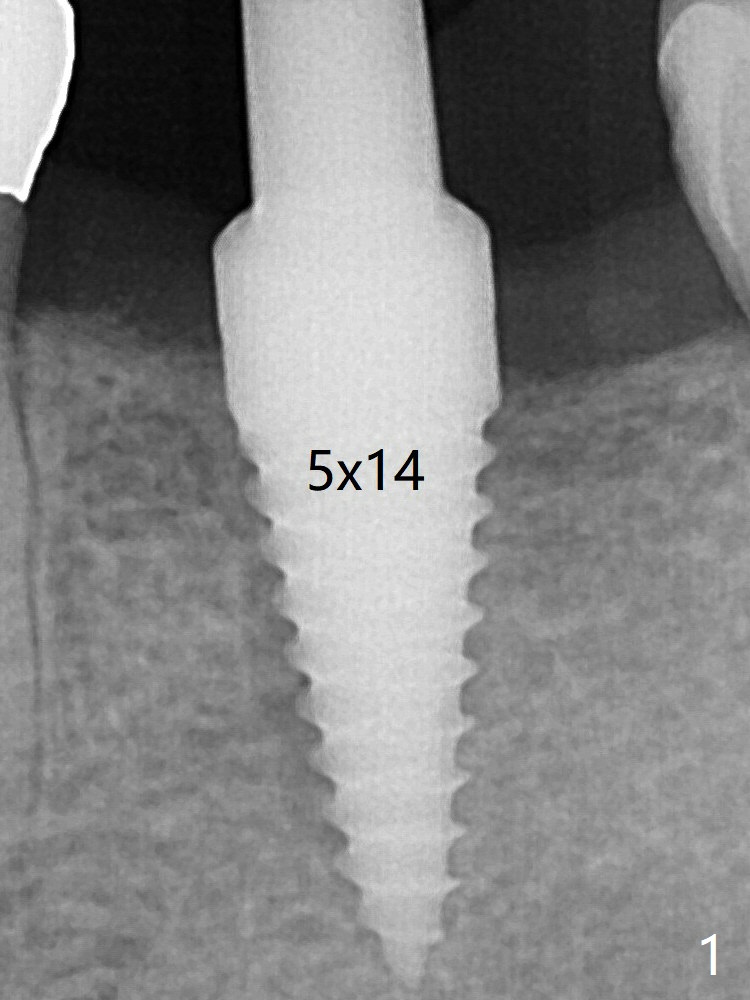

病人抱怨用临时牙冠咀嚼疼痛,不咬后没有不舒服,其实临时牙冠咬合面穿孔,牙龈正常,永久粘固剂没有外溢(图七)。术后4.5-6个月植体周围骨质吸收(图六,七:箭头)。牙槽嵴处钻洞应与植体直径一样才能减少骨质吸收。